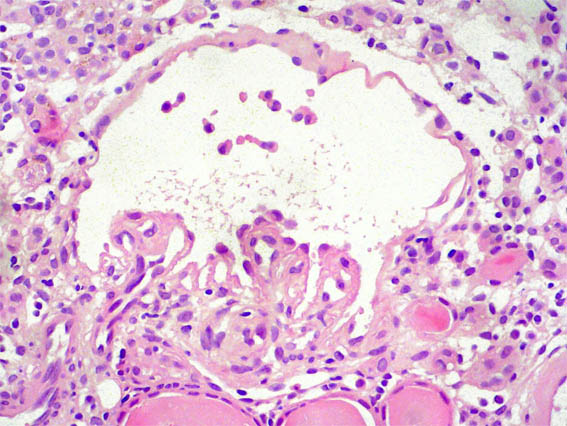

Figura 2.

Plata-metenamina, X200.